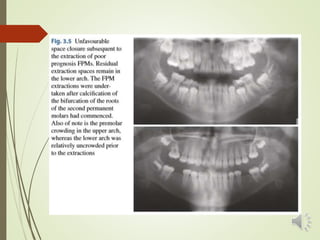

 When a decision is made to extract FPMs in a patient with

little or no need for future orthodontic treatment, a major

consideration is how to avoid residual extraction spaces

remaining in the buccal segments of the patient’s dentition.

 FPM extraction spaces are primarily closed by mesial

migration of the second permanent molars.

 In the upper arch, extraction spaces are more likely to close

spontaneously, through the U 7s drifting mesially and

rotating mesiopalatally, The spontaneous closure of

extraction spaces in the lower arch is less predictable, and

the L 7s have a tendency to tip mesially, with significant

space remaining.